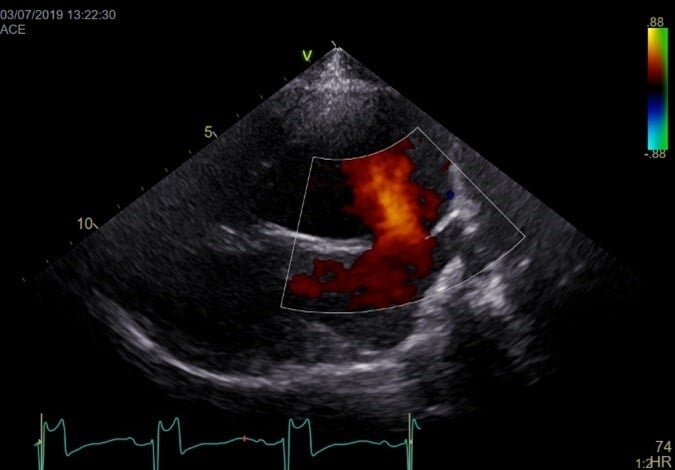

Echocardiography shows an anechoic portion of the atrial septum through which colour Doppler might demonstrate blood flow (Figure 3).

The location of the defect depends on the type of ASD. Ostium secundum ASD is the most common and is localised in the dorsal region of the septum. Flows across the defect are often laminar (not turbulent; normal velocities). Often, an artefactual echo dropout at the level of the atrial septum can mimic an ASD in two-dimensional echocardiography. A patent foramen ovale can also result in blood shunting; however, a membrane is usually visible (no anechoic region).

A bubble study can show if there is right-to-left shunting with direct visualisation of bubbles going from the right to the left atrium.